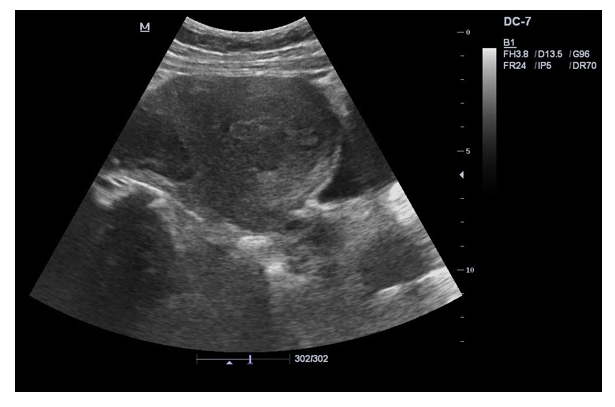

Ultrasound: Abdomen & Pelvis: Normal appearing uterus, with obliterated recto-uterine pouch and intraperitoneal fluid with right sided endometrioma. |

Complete obliteration of the pouch of Douglas and bladder was densely adherent to the lower uterus with free fluid in the peritoneal cavity right sided endometrioma |

Cul de sac biopsy: Multiple cuboidal glands , columnar glands of endometrial origin, suggestive of endometrio sis. |

Patient C had complete obliteration of the pouch of Douglas and bladder was densely adherent to the lower uterus right sided en-dometrioma with free fluid in the peritoneal cavity. The histopa-thology of Cul de sac biopsy showed multiple cuboidal glands and columnar glands with endometrial origin suggestive of endome-triosis. The patient treated with gonadotrophin releasing hormone analogues and there was complete resolution of symptoms in 6 months.

Gonadotropin analogues are widely used as a way to induce hypoestrogenism, causing regres¬sion of the ectopic endometrial tissue [9,20-22]. In our case series, the patient C was diagnosed with endometriosis and right sided endometrioma.( Figure:2) She was treated with gonadotropin re¬leasing hormone analogues, which resulted in complete resolution of symptoms in 6 months [20-22]. Ovarian fibromas are benign ovarian tumors [10]. These tumors are composed of spindle, oval, or round cells forming variable amounts of collagen [23-25]. The patients usually present with as¬cites pleural effusion and abdominal pain [10,23,24]. In this case series patient D presented with abdominal distension, secondary to ascites. After confirming the diagnosis, she underwent right sided oopherectomy with complete resolution of symptoms [23-25].

Figure 3: Endometriosis with Right Sided Endometrioma